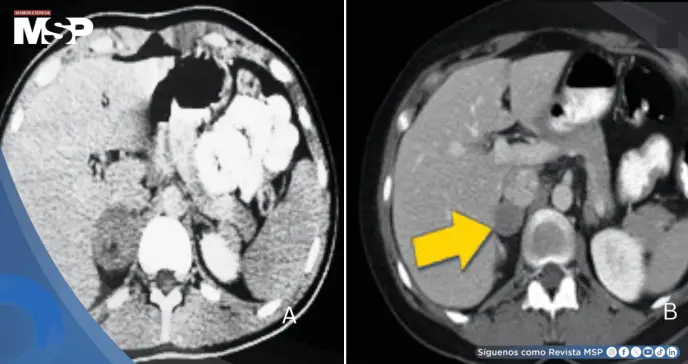

Los estudios específicos revelaron metanefrina plasmática de 4.03 nmol/L (normal <0.5) y normetanefrina de 3.78 nmol/L (normal <0.9), representando elevaciones superiores a ocho veces el límite normal, altamente sugestivas de feocromocitoma.

El diagnóstico de feocromocitoma se estableció definitivamente mediante la demostración de elevación marcada de metanefrinas plasmáticas, específicamente metanefrina y normetanefrina, ambas elevadas más de ocho veces por encima del valor de referencia.

Este hallazgo bioquímico, en conjunto con la presentación clínica característica de hipertensión severa, cefalea, diaforesis y síntomas neurovegetativos, confirma la presencia de un tumor productor de catecolaminas.